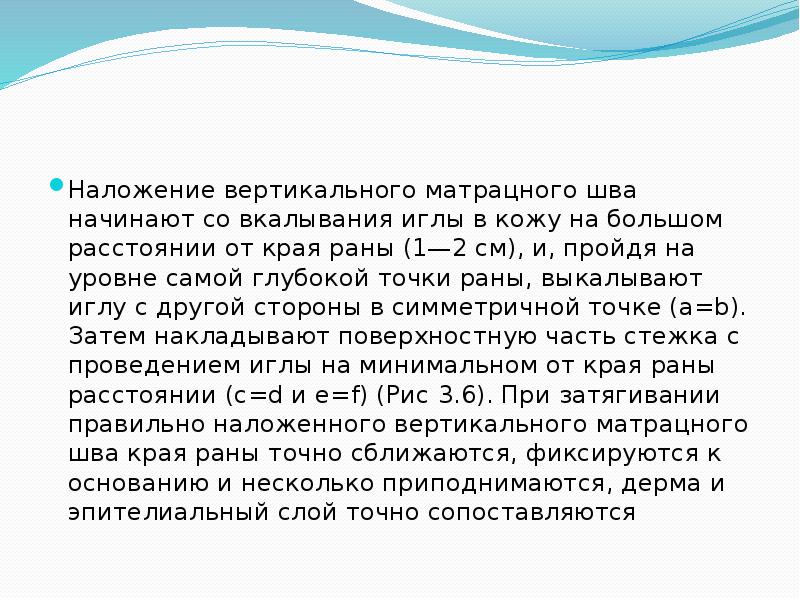

- 29. Вертикальный матрацный шов (шов Донати) узловой вертикальный шов с массивным захватом подлежащих

- 30. Наложение вертикального матрацного шва начинают со вкалывания иглы в кожу на